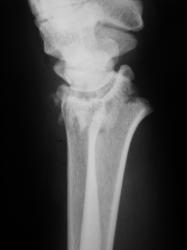

Маловато будет. Дополняю... Со смещением к тылу под углом и по ширине, плоскость эпифиза лучевой кости открыта к тылу под углом *** градусов (стояние отломков неудовлетворительное). Разрыв дистального луче-локтевого сустава.

Отвечаю как коллеге. ///Что есть что? Когда можно говорить о неудовлетворительном или наоборот?/// Точных данных под рукой нет, очень велика доля субъективизма. Общее правило: "Ну, не нравится мне это!!!". Все смещения по ширине просто отмечаю, в долях (1/4, 1/3, 1/2) от поперечника кости, Главное, стояние оси. Угловые смещения до 10 градусов считаются допустимыми. Плоскость эпифиза лучевой кости в норме открыта кпереди под углом 5-10 град. Горизонтальное положение можно считать допустмым. Небольшой наклон плоскости эпифиза кзади - можно считать относительно допустимым, но должен отмечаться в протоколе http://www.radiomed.ru/content/travma-pierielom-biez-smieshchieniia-kostnykh-otlomkov. Представленный случай ни в какие ворота не лезет: тут верные 25 град., более того предположительная ось кисти проецируется за пределы заднего края лучевой кости.

Хирург не ошибся, перелом классический, "луча в типичном месте", как любят писать травматологи. Да еще и внутрисуставной, оскольчатый.